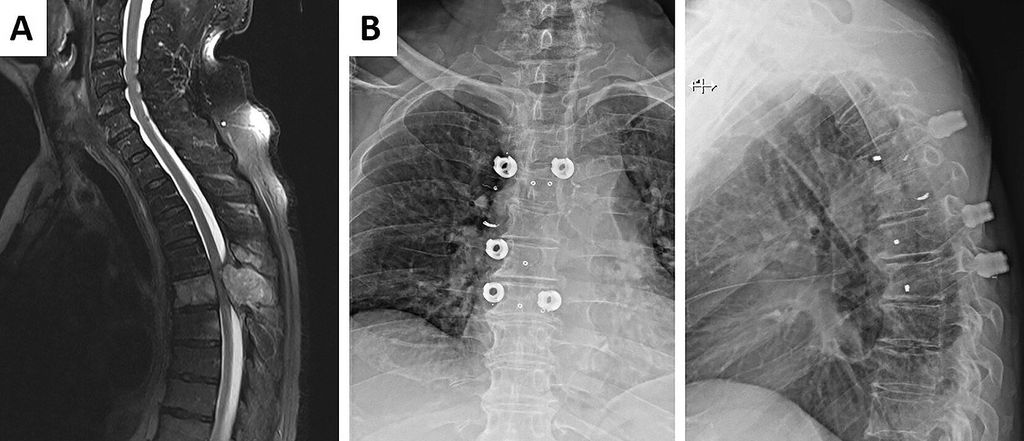

Bei Patienten in guter Allgemeinverfassung und mit guter Prognose ist die Therapie der Wahl die chirurgische Dekompression (Abb.1) mit anschließender Strahlentherapie bei abgeheilten Verhältnissen. Eine chirurgische Intervention kann auch zur Diagnosefindung (Biopsie) und/oder Stabilisation einer instabilen (schmerzhaften) Fraktursituation angezeigt sein. In seltenen Fällen mit solitärer spinaler Metastase, gutem Gesundheitszustand und höherer Lebenserwartung ist eine En-bloc-Tumorresektion mit Stabilisierung als „kurativer Ansatz“ in Erwägung zu ziehen.7 Prognostisch günstige Faktoren bzgl. des Outcomes einer chirurgischen Intervention sind:5

Abb. 1: A) MRT bei akuter Querschnittsymptomatik aufgrund einer Metastase eines Nierenzellkarzinoms (NCC) von BWK 5. Es zeigt sich eine absolute Spinalkanalstenose. B) Postoperative Röntgenaufnahmen a/p und seitlich. Die Versorgung erfolgte in Form einer Laminektomie sowie mit dorsaler Stabilisation (mit Carbonimplantaten, zur Reduktion der Streustrahlung bei späterer Strahlentherapie). 24 Stunden vor dem Eingriff wurde eine Embolisation zur Blutungsprophylaxe bei NCC durchgeführt (siehe Coil auf Höhe der Metastase BWK 5 rechts)

In Fällen mit singulärer Metastase der WS, in welchen eine Operation aufgrund oben genannter Befundkonstellation indiziert war, wurde die signifikante Überlegenheit eines chirurgischen Vorgehens hinsichtlich des neurologischen Outcomes im Vergleich zu alleiniger Strahlentherapie eindrucksvoll nachgewiesen.8